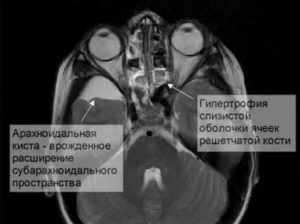

Картина арахноидальных изменений ликворокистозного характера в ходе исследований МР и КТ показывает наличие очагов с плотностью цереброспинальной жидкости, что подтверждает кистозную, неопухолевую природу образования.

Несмотря на то, что КТ позволяет точно определить размеры и расположение кисты, наиболее точную и полную информацию об образовании дает МРТ. Обычно для диагностики арахноидальной кисты проводится МРТ-сканирование с введением в кровоток пациента контраста.

При этом опухоли мозга имеют свойство накапливать контраст, а кисты не впитывают его из кровеносных сосудов, что очень четко видно на МРТ.

Также МРТ-сканирование позволяет отличить кисту от кровоизлияний, гематом, гигром, абсцессов и других заболеваний со сходной симптоматикой. Кроме того, МРТ дает возможность выявить кисту даже в тех случаях, когда у пациента еще нет никаких проявлений, а сама киста имеет размеры всего в несколько миллиметров.